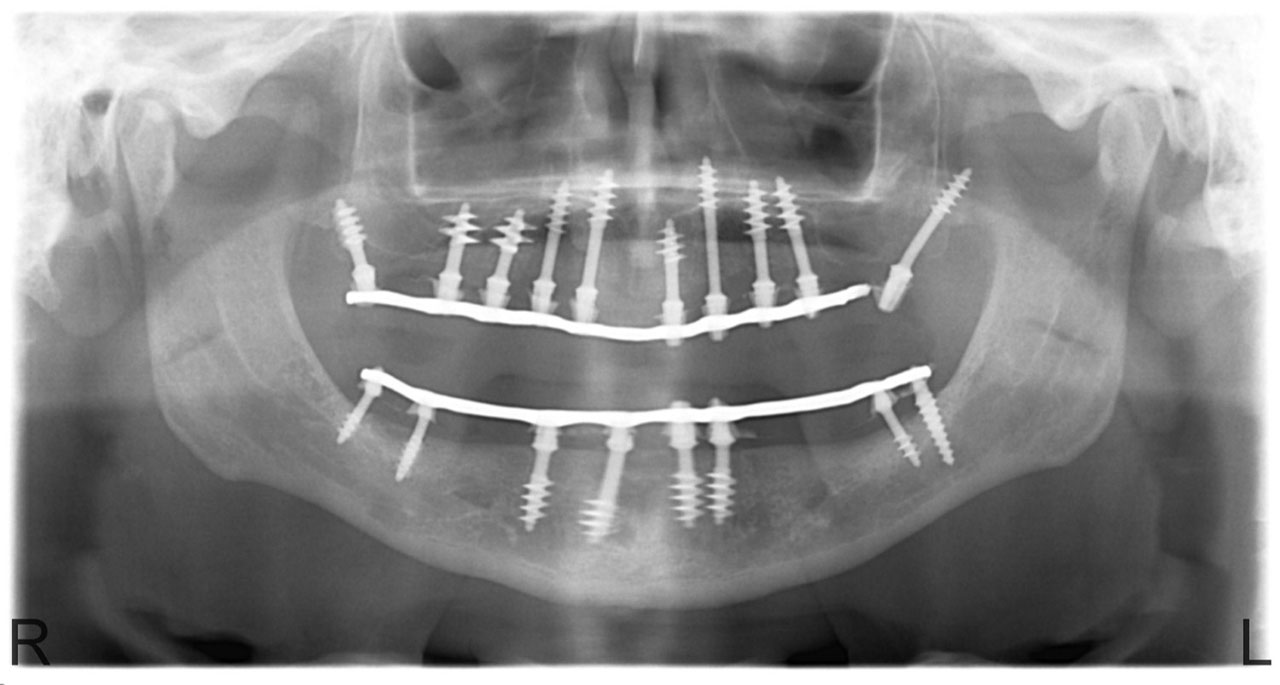

• esettanulmany-14

Alsó- felső fogatlan állcsont teljes implantációs helyreállítása.